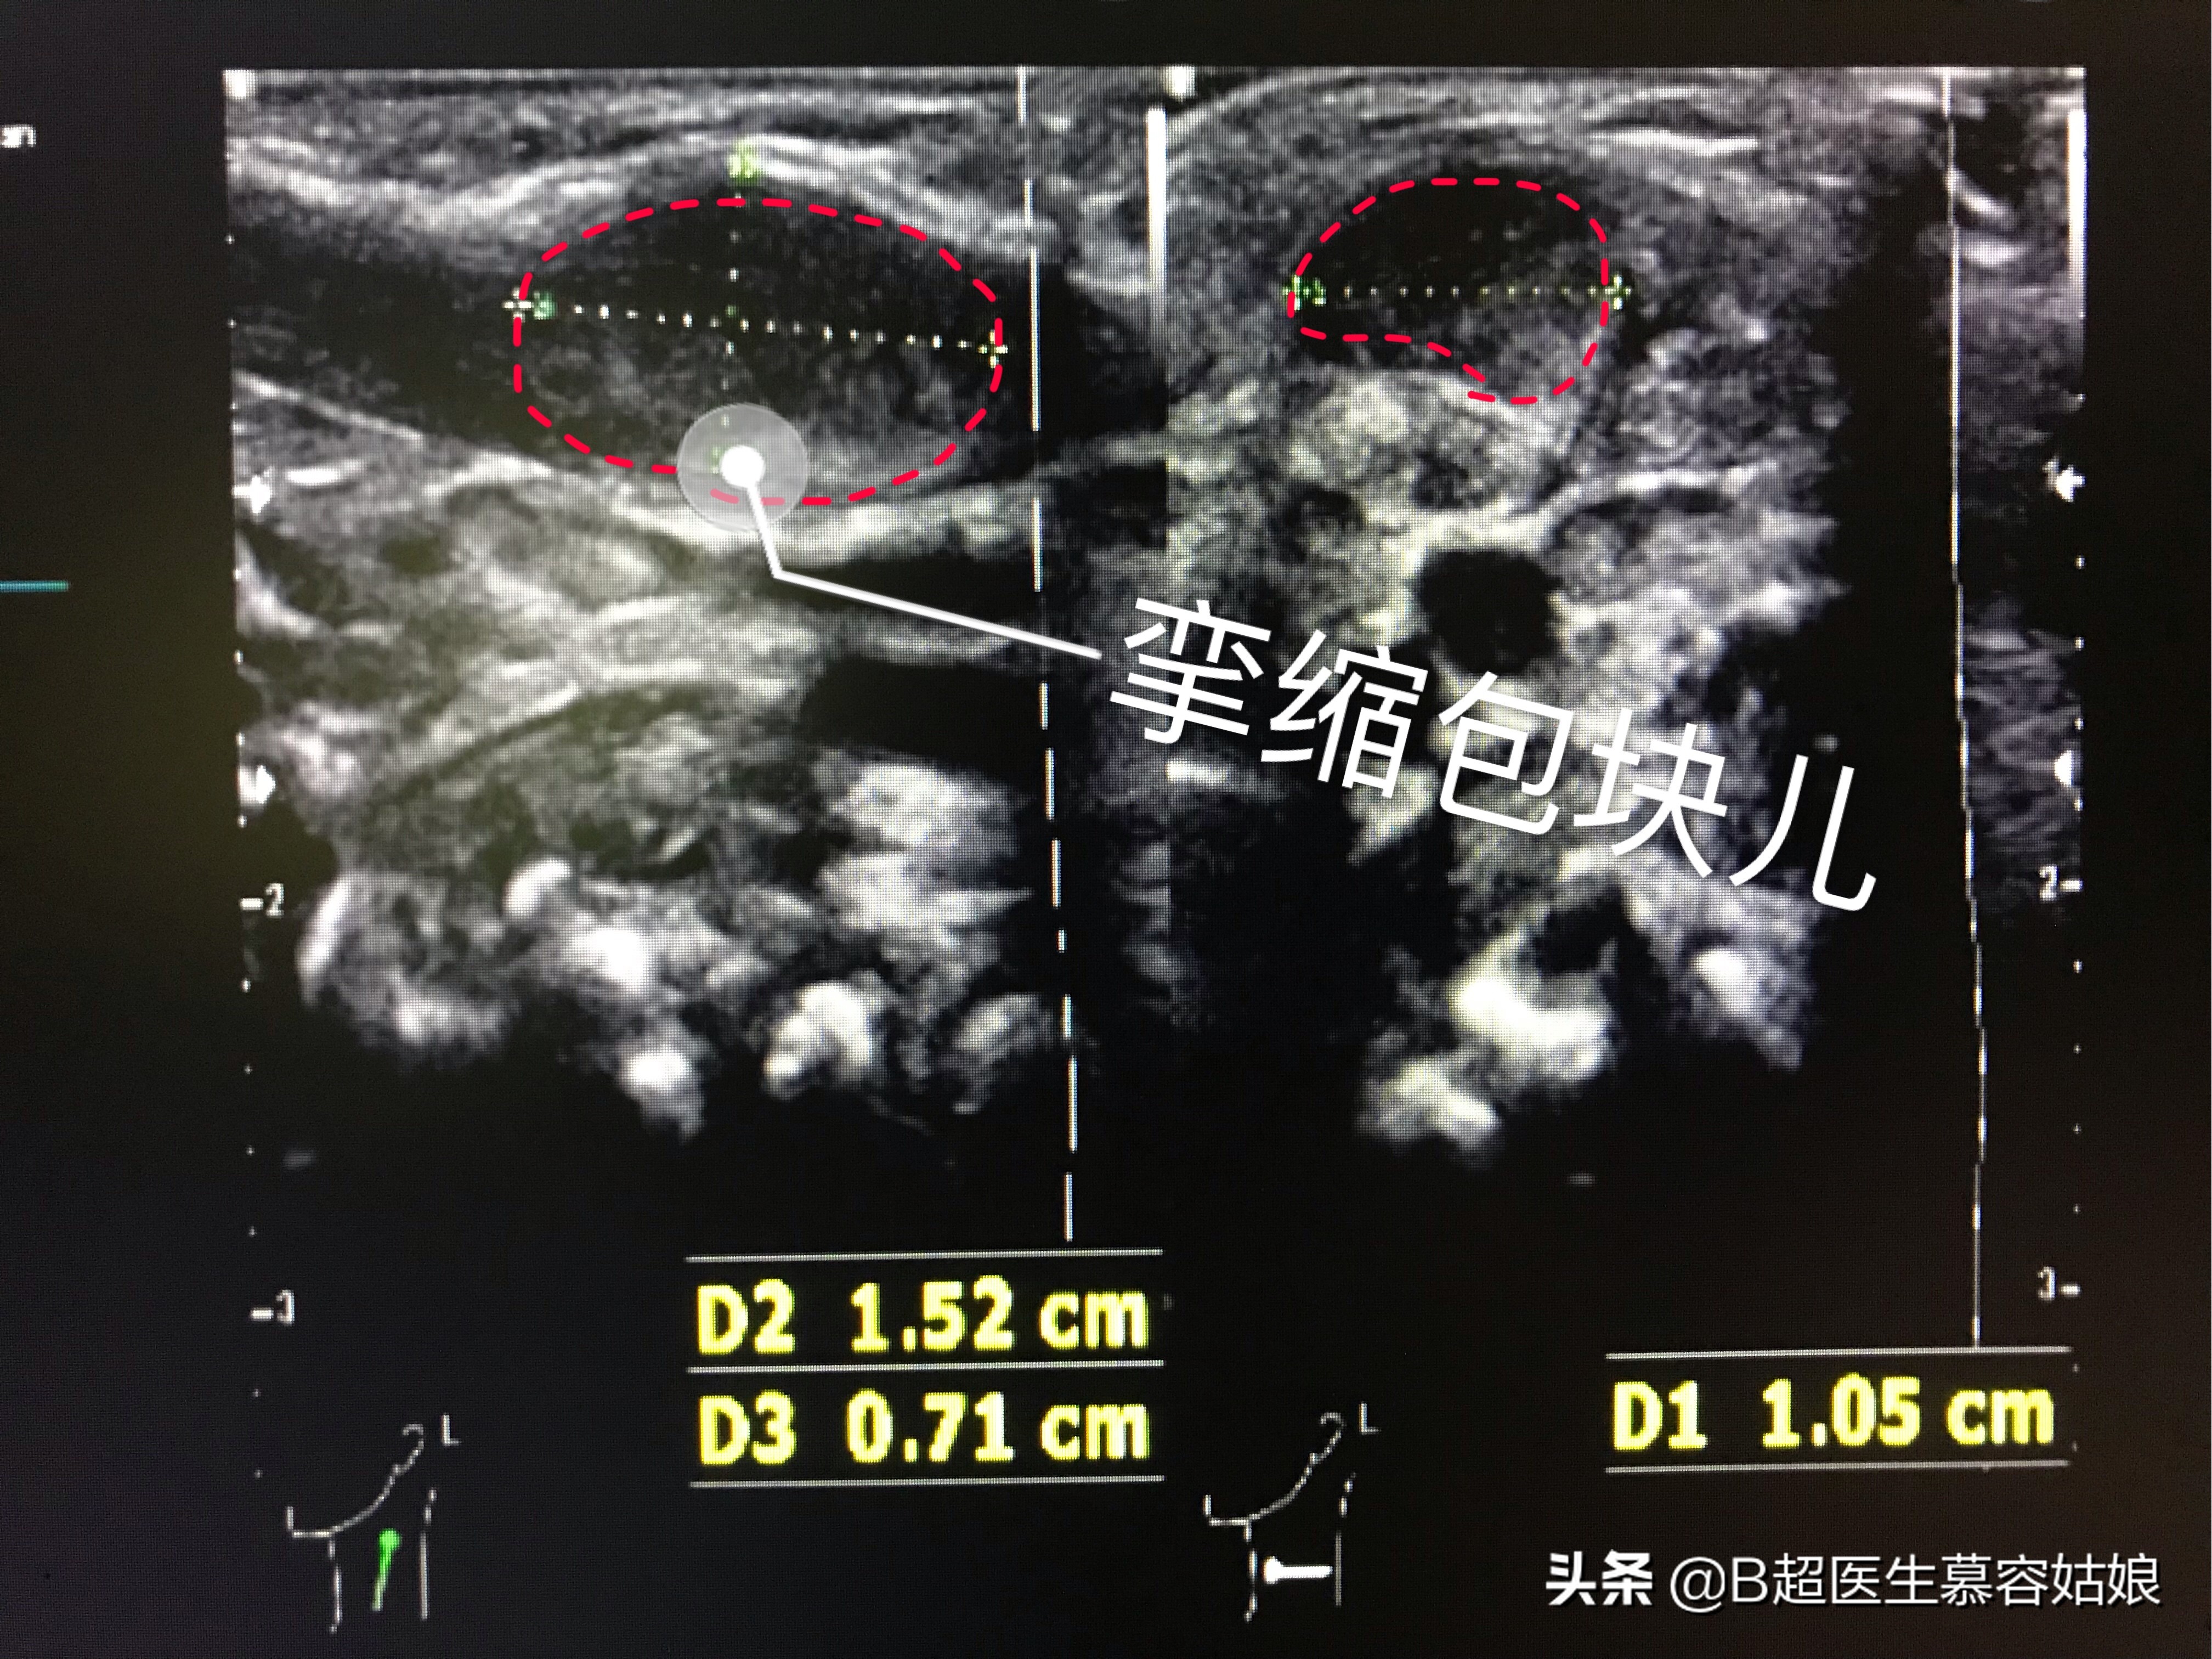

给他用超声波检查了才发现,原来宝宝的左侧胸锁乳突肌上面有一个包块儿,大小约1.5*1.0*0.7cm。如下图:

宝宝左侧胸锁乳突肌上有一个挛缩包块儿

而给宝宝右侧胸锁乳突肌也扫查了一下做对比,发现右侧胸锁乳突肌非常平滑,是正常的平滑的肌纤维图像,如下图:

这是宝宝右侧胸锁乳突肌,正常的形态是平滑的。